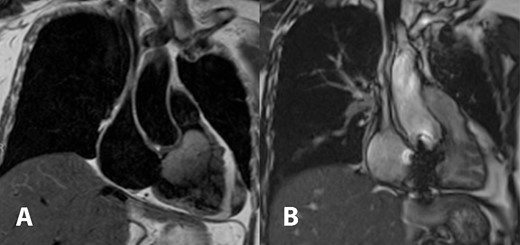

Cardiac magnetic resonance imaging showed a partially mobile mass measuring 60 × 39 × 46 mm within the right ventricular cavity. The mass is isosignal on T1-weighted images, hyperintense signal on T2-weighted images (Fig. 1A), and hyperintense signals on T2 fat-suppression sequences. It obstructed the right ventricular outflow tract, abutting the right ventricular wall without definite invasion, likely extending from the right atrium, although a stalk was unidentified. First-pass perfusion imaging indicated a normal myocardial perfusion pattern with heterogeneous vivid enhancement of the mentioned mass. Tricuspid valve regurgitation was observed, and the right ventricular ejection fraction was 14% while the left ventricular ejection fraction was 70%.

Cardiac magnetic resonance imaging demonstrated T2 hyperintense partially mobile 60 × 39 × 46 mm mass occupying the right ventricular cavity and causing outflow tract obstruction (A). Comparison to post-surgical resection in picture (B) showed decreased right atrial and ventricular size, the tricuspid bioprosthetic valve in place, and right ventricular function returned to normal.

In the follow-up visit on the fourth month after the operation, cardiac magnetic resonance imaging was obtained and showed a significant improvement of the right ventricular ejection fraction from 14% to 68%. There was also a noticeable decrease in the size of the right ventricle. The tricuspid prosthetic valve appeared to have normal function, and no residual tumor was detected (Fig. 1B).